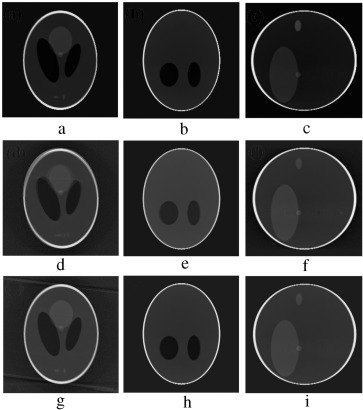

(a–c) Projection at 260°,270° and 280° source position. (d–f) Axial, coronal and ...

Figure 8.

(a–c) Projection at and source position. (d–f) Axial, coronal and sagittal slices of the rotational motion corrupted reconstructed volume.

5. Simulation of the marker-based system

In order to validate the functionality of our proposed Marker-Based Motion Detection (MBMD) and artifacts mitigation technique (MB_FDK algorithm), we need to first simulate motion artifacts using our modified 3D Shepp–Logan phantom. For simulating motion artifacts, we need to perturb the 3D Shepp–Logan phantom during data acquisition time. Using the modified X-ray projection equation  [17] , which incorporated three translational and three rotational (roll, pitch, yaw ) parameters of motion, we simulated several abrupt and gradual variations of motion on the 3D Shepp–Logan phantom. The cone-beam parameters listed in Table 2 are used for our simulation. For abrupt variation of motion, we perturbed the 3D Shepp–Logan phantom with three different types of motion (translational, rotational, and rotational & translational combined) in three different test cases. Some of the images of motion corrupted projections and the axial, coronal and sagittal slices of the reconstructed volume of the above cases are plotted in Figure 7 , Figure 8  and Figure 9 . For gradual variation of motion, we varied each parameter of motion separately in six different test cases. For gradual translational motion corruption cases, we gave ±6 mm of perturbation with a step size of ±1 mm. For gradual rotational motion corruption cases, we gave perturbation of ±5° with a step size of ±1°. The axial, coronal and sagittal slices of the gradual motion corrupted cases (+ perturbation only) are plotted in Figure 10a  and Figure 10b . Figure 10a  and Figure 10b show the motion artifacts created in the reconstructed image due to the gradual perturbation given to the 3D Shepp–Logan phantom during data acquisition time. In Figure 10a , the 1st row shows the artifacts occurred due to the perturbation of +6 mm with a step size of +1 mm along the -axis given. The 2nd and 3rd rows show the artifacts created due to the similar perturbation given to the phantom along the and axes, respectively. In Figure 10b , the 1st row shows the motion artifacts (artifacts dominant in the axial slice) occurred due to the rotational perturbation of 5° (clock-wise) with a step size of 1° given about the -axis (yaw). The 2nd row shows the motion artifacts (artifacts dominant in the sagittal slice) occurred due to the same rotational perturbation about the -axis (pitch). The 3rd row shows the artifacts (artifacts dominant in the coronal slice) occurred due to the rotational variation of similar motion about the -axis (roll). From Figure 7 , Figure 8 , Figure 9 , Figure 10a  and Figure 10b , it can be observed that head motion during data acquisition time resulted in doubling, ghosting, blurring and loss of resolution artifacts in the reconstructed images.